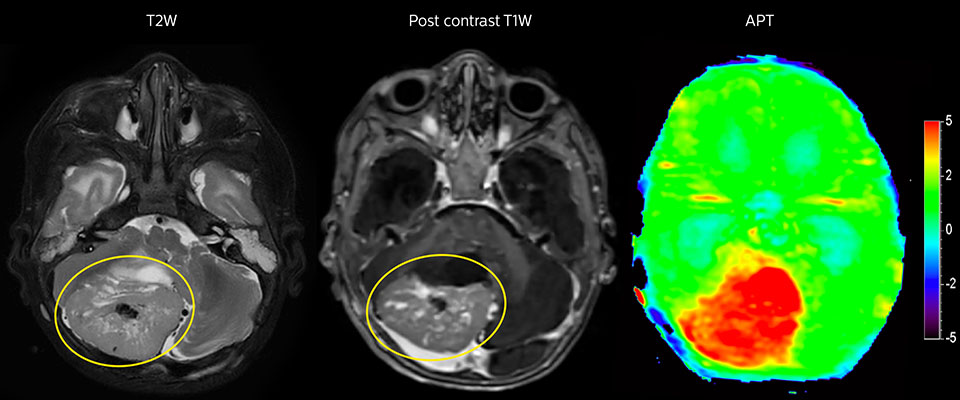

APT imaging of high-grade tumor

Tumor evaluation in a 1-year-old child with medulloblastoma. This aggressive tumor type is very solid and homogeneous. The high APT signal corresponds with the post-contrast image of this high-grade tumor.

APT may be a powerful addition to grade tumors with MRI